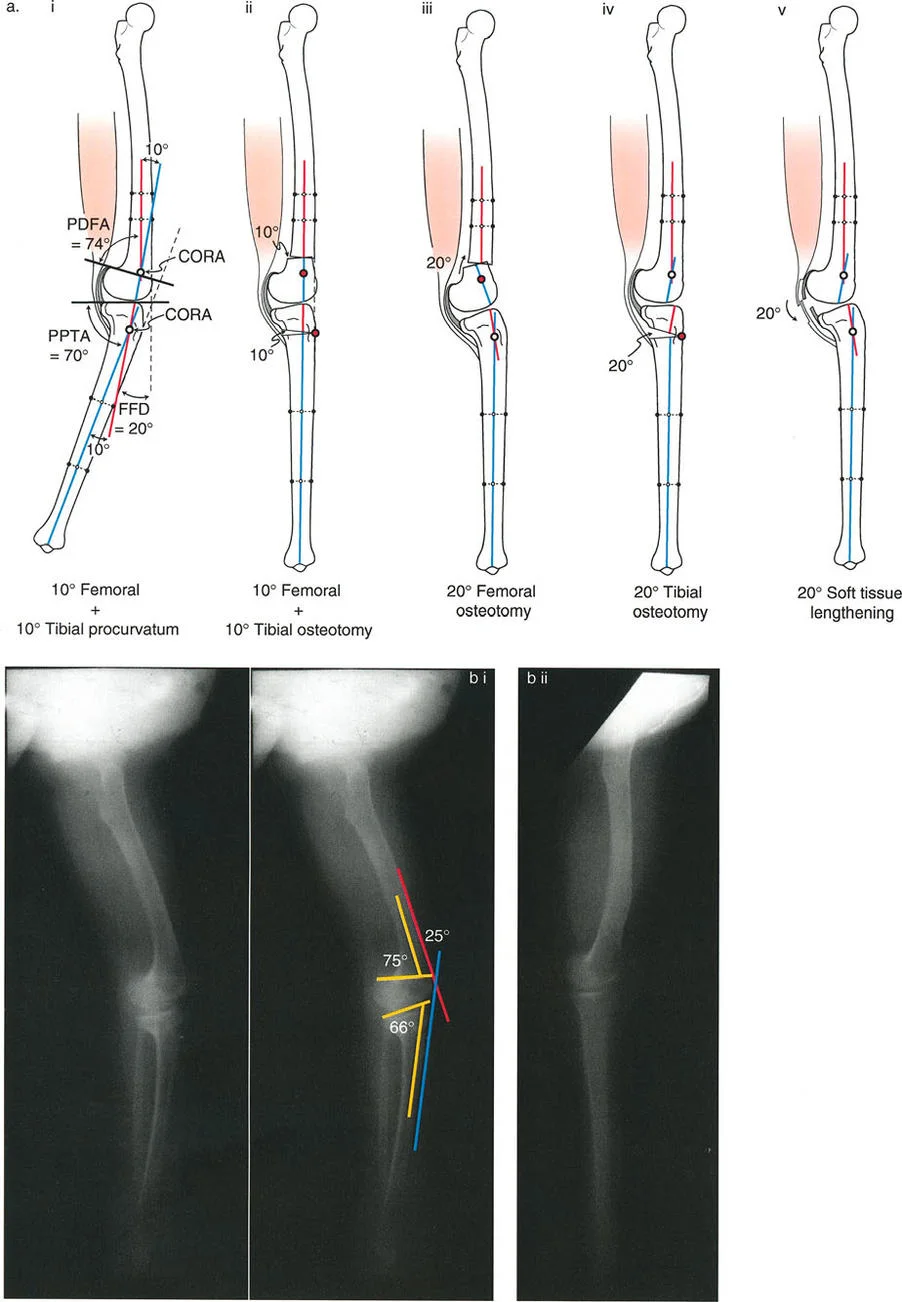

- الأشعة السينية الطويلة للطرف السفلي بالكامل أثناء الوقوف (Standing Long-Leg AP View): تُعد هذه الأشعة حاسمة لتقييم المحاذاة الميكانيكية للطرف السفلي بأكمله. تُظهر بدقة درجة الانحراف الأفحج (Varus) أو الأروح (Valgus) وتساعد في تحديد مركز دوران التشوه (CORA).

- الأشعة الجانبية الطويلة للطرف السفلي بالكامل أثناء الوقوف في أقصى بسط (Standing Long-Leg Lateral View in Maximum Extension): تُستخدم لتقييم تحدد حركة الركبة (FFD) والركبة الارتدادية (Recurvatum)، وتحديد ما إذا كان التشوه عظميًا أو ناتجًا عن تقلص في الأنسجة الرخوة.

تتضمن جراحة قطع العظم قطع العظم (عادة عظم الفخذ أو الساق) وإعادة تشكيله لتغيير محاذاة المفصل. يمكن أن يكون القطع:

تصحيح تحدد حركة الركبة (Flexion Deformity - FFD)

تحدُّد حركة الركبة هو عدم القدرة على مد الركبة بالكامل. يمكن أن يكون سببه عظميًا أو ناتجًا عن تقلص في الأنسجة الرخوة.

- التشخيص الدقيق: يجب تحديد ما إذا كان تحدد الحركة ناتجًا عن تشوه عظمي (تقوس أمامي في الفخذ أو الساق) أو تقلص في الأنسجة الرخوة (الأوتار الخلفية، محفظة المفصل).

- قطع العظم التمديدي (Extension Osteotomy):

- إذا كان التشوه عظميًا، يتم إجراء قطع عظم تمديدي في عظم الفخذ أو الساق لتصحيح التقوس.

- الأستاذ الدكتور محمد هطيف يؤكد على أهمية عدم تصحيح الساق بأكثر من 90 درجة PPTA لتجنب فقدان الميل الخلفي الطبيعي للساق.

- تحرير الأنسجة الرخوة (Soft Tissue Release):

تصحيح الركبة الارتدادية (Recurvatum Deformity - Hyperextension)

الركبة الارتدادية هي فرط البسط في الركبة. غالبًا ما تكون غير مصحوبة بأعراض في الأشخاص ذوي العضلات السليمة، ولكنها قد تسبب مشاكل في حالات ضعف العضلات أو التشوهات العظمية.

- التشخيص: يجب تحديد ما إذا كانت الارتدادية عظمية (تقوس خلفي في الفخذ أو الساق) أو ناتجة عن رخاوة في الأنسجة الرخوة أو ضعف عضلي.

- قطع العظم الانثنائي (Flexion Osteotomy):

- إذا كان التشوه عظميًا (تقوس خلفي)، يتم إجراء قطع عظم انثنائي في عظم الفخذ أو الساق لتصحيح الارتدادية.

- الأستاذ الدكتور محمد هطيف يشدد على أهمية عدم استخدام قطع عظم الفخذ الانثنائي لتصحيح ارتدادية الساق، والعكس صحيح، لتجنب الانزلاق الخلفي أو الأمامي للركبة.

- اعتبارات خاصة: في المرضى الذين يعانون من ضعف عضلي (مثل شلل الأطفال)، قد يحتاج التصحيح إلى فرط تصحيح بسيط (overcorrection) إلى وضعية انثناء لضمان ثبات الركبة ومنع فرط البسط غير المتحكم فيه.